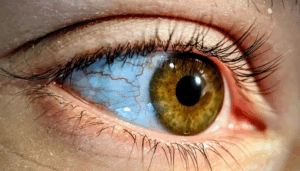

Clear Eyes, Clear Solutions: Treating Pink Eye with an Online Doctor

Pink eye, or conjunctivitis, is more than just a mere inconvenience – it's a condition that can disrupt daily life with uncomfortable symptoms and potential…